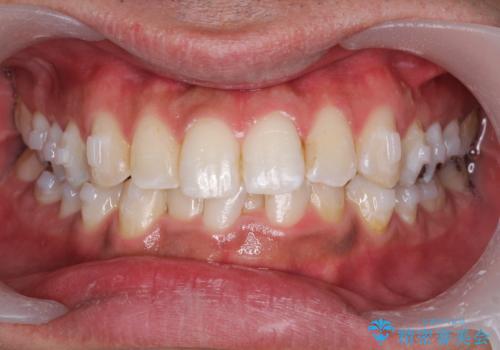

矯正治療前にPMTCで口元のケア